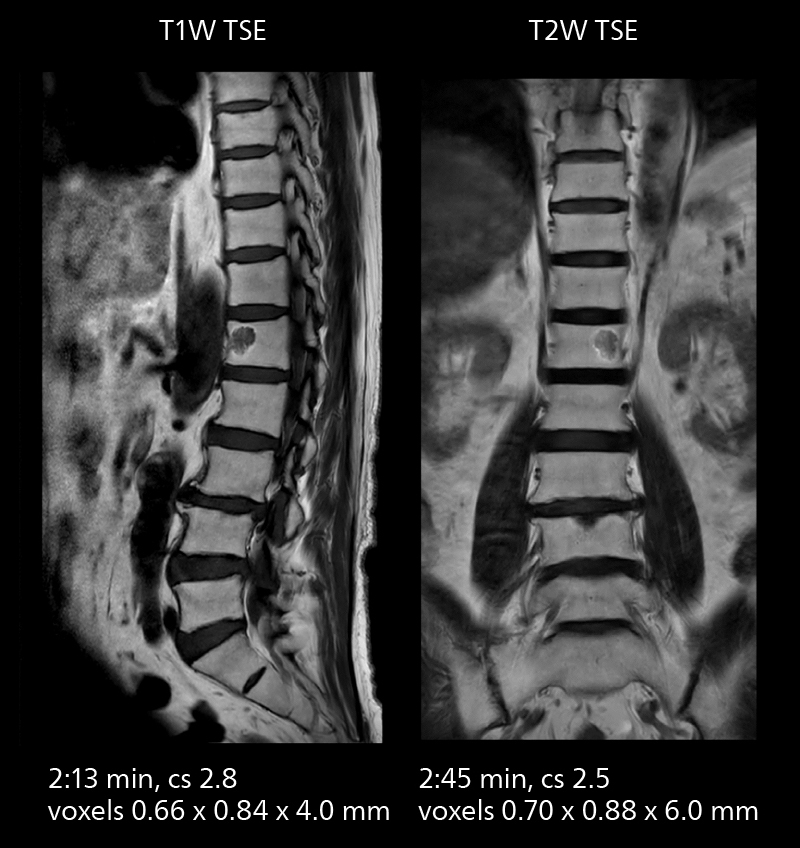

Examples of prostate imaging showing faster scan times and improved resolution illustrate the power of SmartPath to Elition X in this case of prostate cancer with PI-RADS score 4.